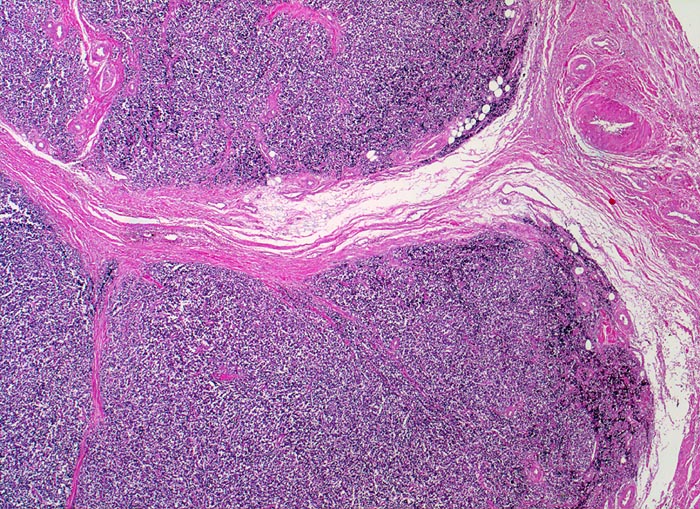

Die Tumoren sind makroskopisch grauweiss und wachsen destruktiv und infiltrativ. Nekrosen und Einblutungen sind häufig. Histologisch lassen sich solide Rasen monomorpher, kleiner, rundlicher Tumorzellen mit dichtem Chromatin und wenig Zytoplasma nachweisen (sog. small-blue-round cells). Metastasen treten vor allem in der Lunge und in anderen Skelettabschnitten auf. Die Differentialdiagnose klein-blau- und rundzelliger Tumoren im Kindesalter ist breit. Kleinzellige Osteosarkome, Neuroblastome, Lymphome und mesenchymale Chondrosarkome können ein histologisch ähnliches Bild zeigen, speziell in kleinen Biopsien, und müssen mit Hilfe von (molekularen) Zusatzuntersuchungen und unter Einbezug klinischer und radiologischer Befunde voneinander abgegrenzt werden.

• Durch Bindegewebssepten abgegrenzte Knoten (lobuläre Architektur).

• Blauer, klein- und rundzelliger Tumor.

• Uniforme Zellen mit schmalem, kaum abgrenzbarem Zytoplasmasaum und unscharfen Zellgrenzen. Rundliche oder ovale Zellkerne mit leicht vergröbertem Chromatin und punktförmigen kleinen Nukleolen.

• Quetschartefakte (gequetschte Zellen sind dunkler und haben verkleinerte abgeflachte Zellkerne).